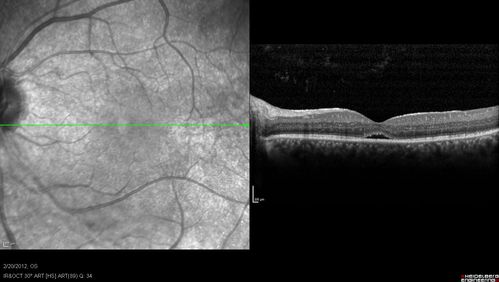

Retinitis Pigmentosa Sine Pigmento or Unknown Dystrophy - Peripheral Superficial White Spots and Recurrent CME

1 month of treatment with diamox 500 mg BID- cme is a little better